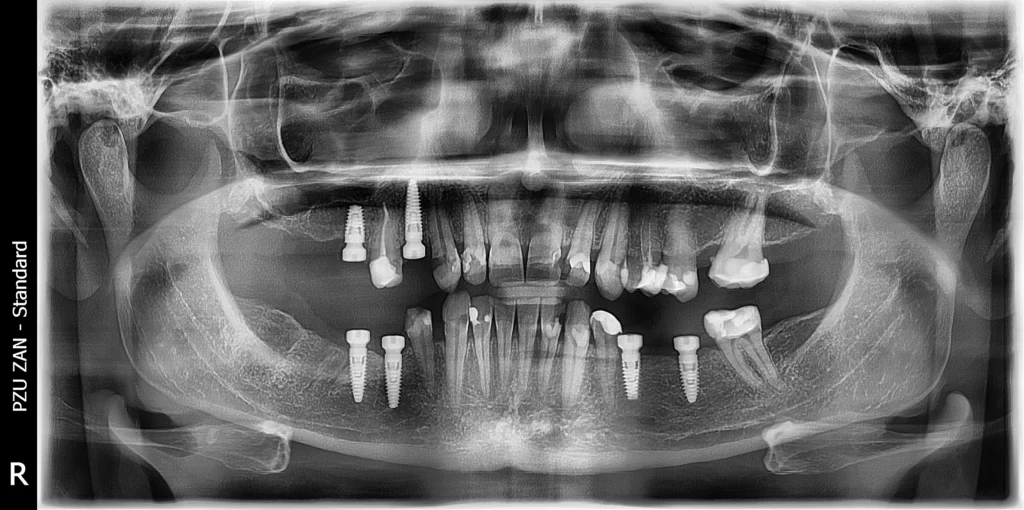

After a thorough clinical examination and advanced 3D CBCT imaging, we carefully analyzed her condition and created a fully personalized treatment plan.

The solution included a combination of dental implants, crowns, and bridges—designed to restore both function and aesthetics in the most natural way possible.

In the first phase, we placed six dental implants using computer-aided surgical guides. This technology allowed us to achieve exceptional precision, ensuring optimal positioning, stability, and long-term success of each implant.